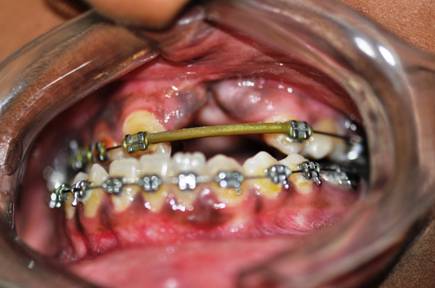

MAXILLARY LEFORT I ADVANCEMENT

BILATERAL SAGITAL SPLIT OSTEOTOMY SETBACK |